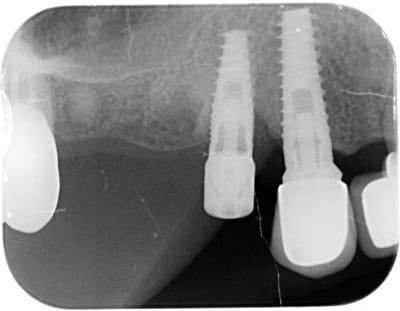

Quelqu'un saurait-il m'indiquer la marque de l'implant en 14 SVP, celui avec le pilier de cicatrisation?

çà ressemble à de l'IDI

https://www.spotimplant.com/fr/implants-dentaire/idi-dental/id-bio

Si tu regardes bien la radio….amha il y a un multiunit dessus avec une vis de confort….